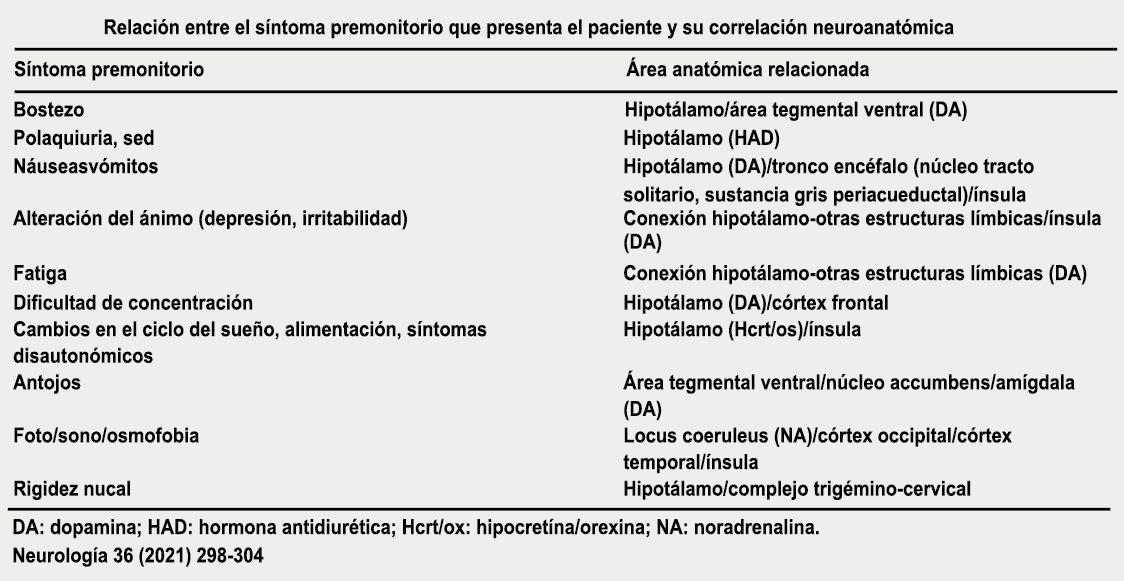

Todo lo mencionado contribuye al fenotipo del migrañoso y son vías que continuamente se están explorando para el desarrollo de nuevas terapias agudas y preventivas del dolor, más seguras y eficaces. Sin embargo, existe una controversia que gira en torno a dos cuestiones: la iniciación y el origen del dolor además de que todavía no se conoce el origen de los mecanismos neuronales que subyacen a la condición primaria en las personas susceptibles. Definitivamente la migraña implica la activación y sensibilización de las vías trigeminovasculares, así como el tronco cerebral y los núcleos diencefálicos(88). La vía aferente comienza en las aferentes vasculares nociceptivas de la duramadre que están para advertir, no para localizar. Su proyección al tálamo y la corteza y como se regula esta vía en cada nivel y por múltiples sistemas, ofrece la posibilidad de comprender los síntomas complejos y orientar las terapias. Los ataques comienzan como síntomas premonitorios, dificultad para concentrarse, bostezos, fluctuaciones del humor; y cambios homeostáticos, como la alimentación y el equilibrio de líquidos, que pueden incluir sensibilidades más generalizadas, como fotofobia y fonofobia. La fase premonitoria da paso a la fase de dolor con el sufrimiento acompañante y termina en una fase posdrómica de sentirse agotado por la experiencia. (Figura 1)

Los síntomas premonitorios son parte del cuadro clínico que acompaña a los dolores de cabeza en las crisis de migraña. Por definición, ocurren antes del inicio del dolor y son diferentes del aura de la migraña. Los síntomas premonitorios más frecuentemente reportados fueron sensación de cansancio y agotamiento (72%), problemas de concentración (51%) y rigidez de nuca (50%). Menos comunes, pero de manera importante, asociados con una mayor previsibilidad de los ataques de migraña fueron los bostezos, la visión borrosa, la sensibilidad al ruido, las dificultades de la función cortical superior (como leer, escribir, hablar, pensar) y sentirse emocional e irritable. Además, la regulación homeostática parece estar alterada durante la fase premonitoria que se manifiesta con sed, náuseas, hambre, micción frecuente o estreñimiento(36). Este patrón complejo de síntomas ha llevado a la hipótesis de que los síntomas podrían ser de naturaleza hipotalámica y/o cerebrales difusos(37). La mayoría de los migrañosos los experimentan mucho antes de que se inicie la típica migraña, pero que ya le indican al paciente que un dolor de cabeza está en camino. Estas señales premonitorias pueden preceder a la fase de dolor de cabeza hasta 72 horas, también se han informado cambios en el estado de ánimo y la actividad, irritabilidad, fatiga, antojos de alimentos, bostezos repetitivos, rigidez en el cuello y fonofobia. Pueden perdurar hasta bien entrada el aura, la cefalea e incluso las fases posdrómicas. La consistencia de estos síntomas permite a algunos migrañosos predecir de forma fiable sus crisis dolorosas. El hecho de que estos síntomas sean en gran medida de origen hipotalámico, han sido demostrados por estudios de imagen mediante PET con H2O(12).

Curiosamente, muchos de los factores desencadenantes descritos por los migrañosos, como por ejemplo la falta de sueño, el hambre o la luz brillante, pueden representar síntomas premonitorios de un ataque que ya está en curso. (Tabla 1)